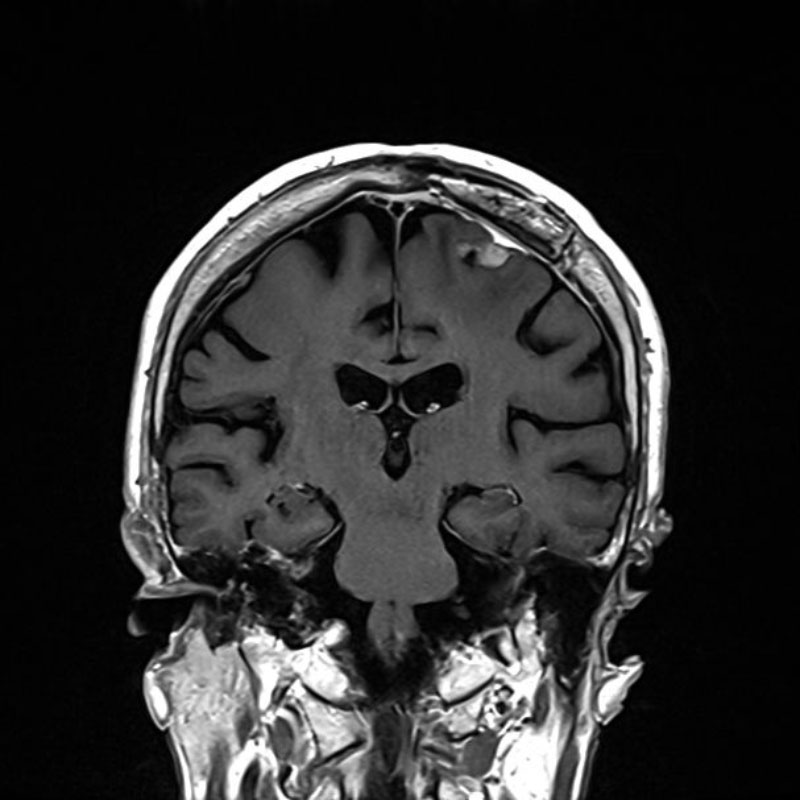

684

'25年10月

50代

右小脳静脈性血管腫

頭蓋内腫瘍摘出術

No.’25_86 手術前1

No.’25_86 手術前2